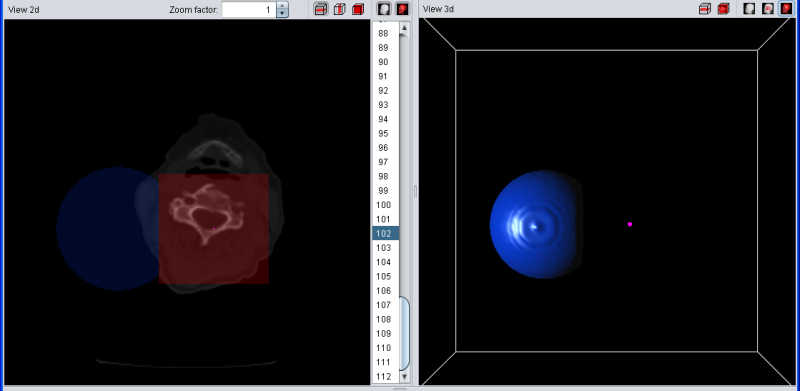

If the selection is "removed" from the segment, all violet voxels turn red. After removing the selection, they do not belong to the blue segment anymore but are still in the selection.

|

| Selection (red) was removed to from segment |